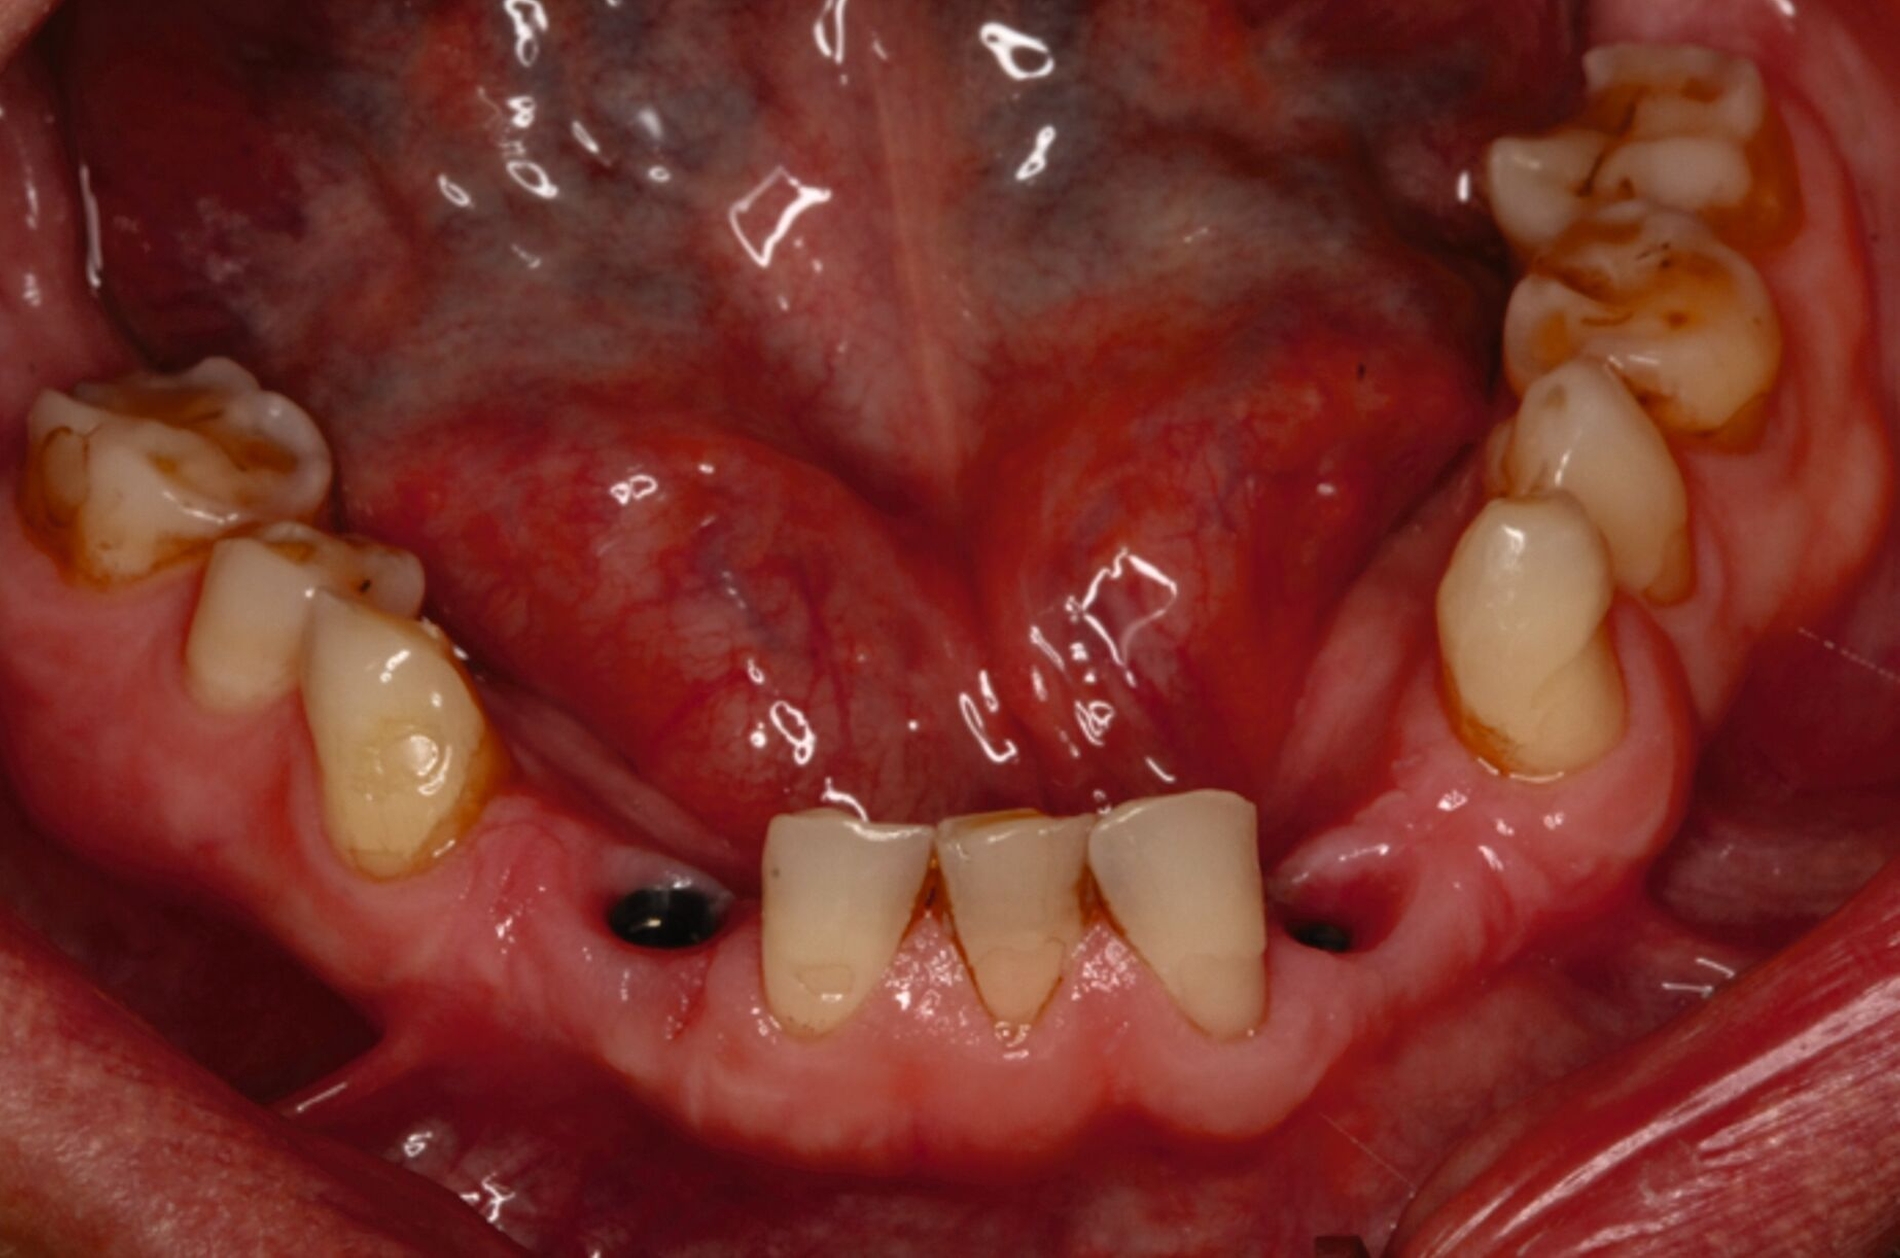

Ein 30-jähriger Patient stellte sich mit multipler Oligodontie (15 fehlende bleibende Zähne), Persistenz von Milchzähnen sowie ausgeprägter Dysgnathie mit progenem Deckbiss vor. Klinisch zeigten sich hypoplastische Restzähne, Fehlstellungen und erhebliche funktionelle Beeinträchtigungen (Abbildung 1). Sein Wunsch bestand in einer möglichst optimalen ästhetischen und funktionellen Versorgung seiner für ihn äußerst unbefriedigenden Gebisssituation. Die molekulargenetische Analyse bestätigte eine homozygote Mutation im WNT10A-Gen als Ursache der Zahnagenesie.

Eine mögliche und indizierte Umstellungsosteotomie wurde vom Patienten abgelehnt. Da seitens des Patienten eine Kopfbissstellung möglich war, wurde eine Bissumstellung und -hebung mit nur noch geringgradigem Vorbiss und anschließender Zahnimplantation in Erwägung gezogen. Begonnen wurde mit einer temporären Schienentherapie zur Neuorientierung der Bisslage (Abbildung 3). Da der Patient die angepasste Bisshebung tolerierte, wurde diese nach Entfernung der persistierenden Milchzähne 55, 53, 52, 62 und 83 temporär mittels einer Valplastprothese (Abbildung 4) als Interimsersatz im Oberkiefer gesichert.